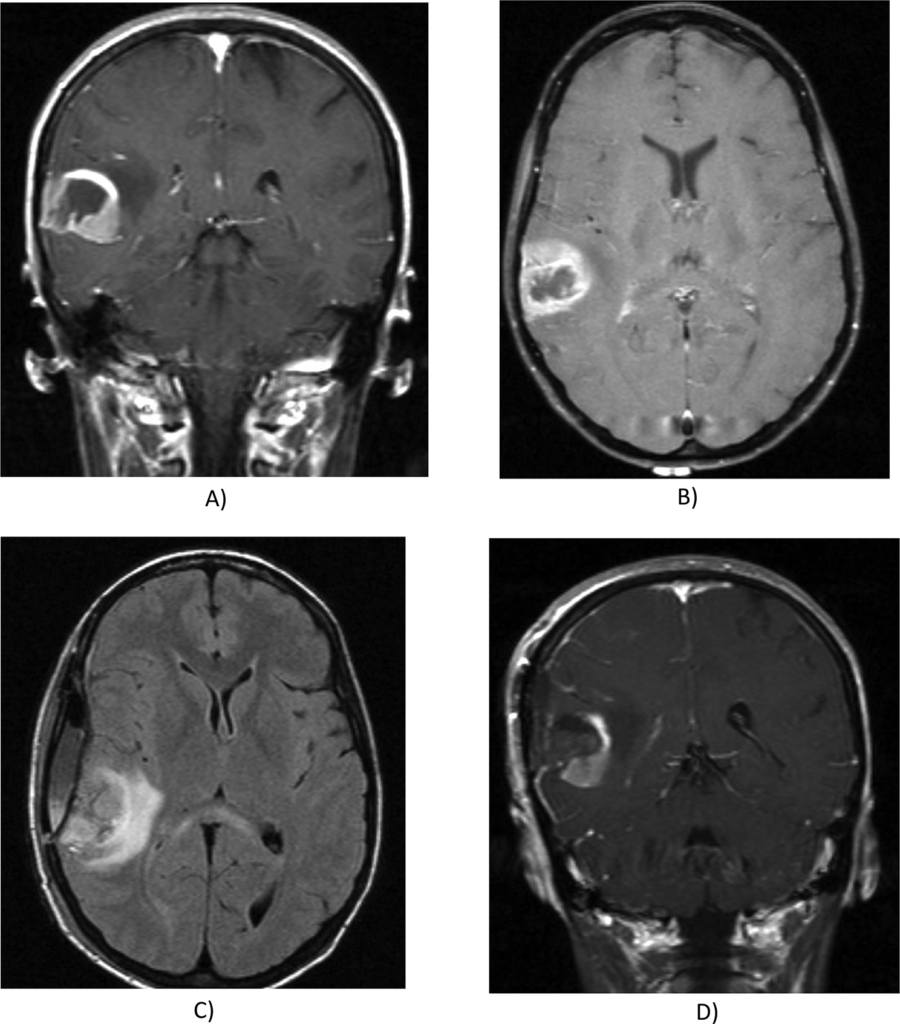

Three board-certified radiologists independently analyzed 33 adult type glioma cases (20 glioblastomas, seven astrocytomas, five oligodendrogliomas, and one undefined subtype glioma) using 26 VASARI features and three additional non-VASARI features. Inter-rater reliability was assessed using Fleiss’ kappa and Gwet’s AC with conditional confidence intervals. Ordinal weighting was applied to relevant features.